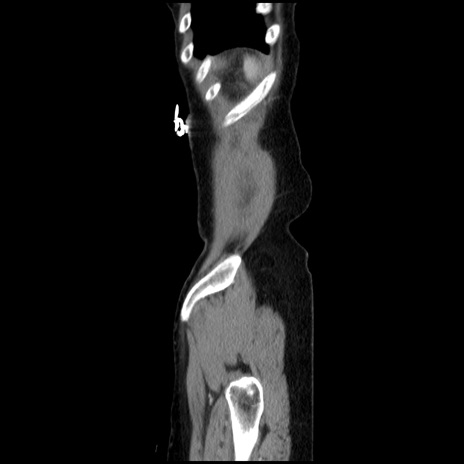

症例32(矢状断像)

【症例】40歳代 女性

【主訴】上腹部痛、嘔気・嘔吐

【現病歴】約9時間前頃から急に上腹部痛、嘔気、嘔吐が出現。改善しないため救急要請。

【既往歴】子宮頚癌(広汎子宮全摘術、放射線療法)、腸閉塞

【身体所見】腹部:平坦、軟、腸雑音亢進、上腹部を中心に腹部全体に圧痛あり。

【データ】WBC 8400、CRP 0.03